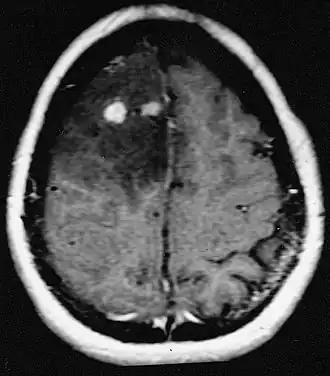

Patiënten lijden aan een verscheidenheid aan karakteristieke symptomen van een focale of multifocale massieve laesie. MRI toont meestal tumoren met homogene contrastversterking in de diepe periventriculaire witte stof. Multifocaliteit en inhomogene versterking zijn typisch voor patiënten met een verzwakt immuunsysteem. Analyse van CZS-lymfoom is uiterst belangrijk bij de differentiële diagnose van hersenneoplasie. Opgemerkt moet worden dat de toediening van corticosteroïden kan leiden tot het volledig verdwijnen van de versterking, waardoor de diagnose van de laesies moeilijk wordt. Als daarom CZS-lymfoom moet worden overwogen bij de differentiële diagnose, moeten corticosteroïden worden vermeden, tenzij het massa-effect een ernstig en onmiddellijk probleem bij de patiënt veroorzaakt.

Hersenmetastasen

Hersenmetastasen zijn de meest voorkomende intracraniële neoplasmata bij volwassenen en komen tien keer vaker voor dan primaire hersentumoren. Ze stappen op 20 tot 40 procent van de volwassenen met kanker en worden voornamelijk geassocieerd met long- en borstkanker en melanoom. Deze laesies zijn het gevolg van de verspreiding van kankercellen door de bloedbaan en komen meestal voor op de kruising van grijze en witte stof, waar de dwarsdoorsnede van bloedvaten verandert, waardoor tumorcelembolie wordt opgesloten . 80 procent van de laesies komt voor in de hersenhelften, procent in het cerebellum en 5 procent in de hersenstam. Ongeveer 80 procent van de patiënten heeft een voorgeschiedenis van systemische kanker en 70 procent heeft meerdere hersenmetastasen.

Hersenmetastasen zijn de meest voorkomende intracraniële neoplasmata bij volwassenen en komen tien keer vaker voor dan primaire hersentumoren. Ze stappen op 20 tot 40 procent van de volwassenen met kanker en worden voornamelijk geassocieerd met long-en borstkanker en melanoom. Deze laesies zijn het gevolg van de verspreiding van kankercellen door de bloedbaan en komen meestal voor op de kruising van grijze en witte stof, waar de dwarsdoorsnede van bloedvaten verandert, waardoor tumorcelembolie wordt opgesloten. 80 procent van de laesies komt voor in de hersenhelften, procent in het cerebellum en 5 procent in de hersenstam. Ongeveer 80 procent van de patiënten heeft een voorgeschiedenis van systemische kanker en 70 procent heeft meerdere hersenmetastasen.